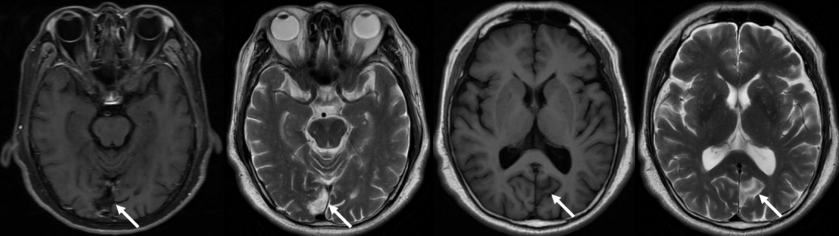

图4 头颅MRI检查

头颅MRI(2022-0218)提示:双侧枕叶梗死(箭头)。

Cranial magnetic resonance imaging(February 18, 2022): Infarction of bilateral occipital lobe(arrow).

结合患者临床表现与眼科检查,入院诊断考虑为双眼玻璃体浑浊,枕叶陈旧性脑梗死;但患者诉既往5年前即诊断双眼玻璃体浑浊,本次起病眼前遮挡呈弥漫小片状,相对固定,无漂浮感,伴视物显小。复查头颅MRI检查提示:双侧枕叶梗死,右侧枕极部,左侧纹状皮质上前部,与既往头颅MRI检查对比未见明显变化(图4)。因患者既往视野检查中心绝对暗点有明显象限分界表现,复查24-2视野检查提示右眼中心暗点(图3B),完善10-2Humphrey 视野检查提示:双眼左侧视野同向偏盲(图3C),完善Goldmann动态视野检查提示:右眼颞侧新月状视野缺损(图5)。至此,结合患者视觉改变特点及神经影像表现,诊断为双眼同侧偏盲、右眼颞侧新月状视野缺损、双侧枕叶脑梗死。